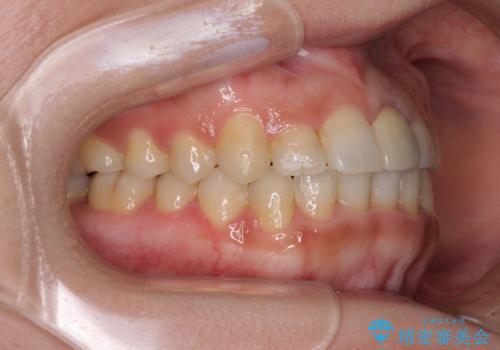

前歯のクロスバイトと変色した歯 ワイヤー矯正とセラミック治療

ワイヤー矯正により矯正治療を行った後に、前歯の補綴治療を行うこととしました。

変色してしまった前歯は、反対側の歯と比べて歯肉が覆い被さっていたため、骨整形を含めた歯周外科処置を行い、歯肉ラインを整えることとしました。